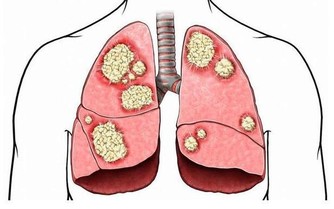

一、中醫裡有這樣一句話「凡是得癌的人都是小腿經絡不暢通;"

但是小腿經絡不暢通不一定是癌症,但一定是疑難雜證比如像牛皮癬,白癜風,魚鱗病,強制性脊椎炎,高血壓,高血脂,高血糖,糖尿病,女士宮寒,痛經,卵巢囊腫,子宮肌瘤,子宮內膜厚,月經量少等症狀都與小腿經絡不暢通有很直接的關系。